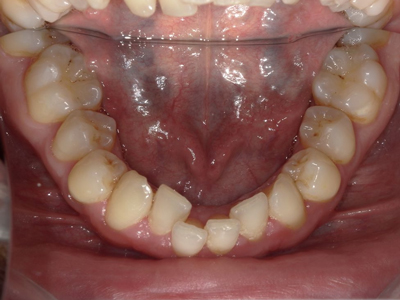

Arcade mandibulaire avant traitement orthodontique, séquelles de maladie parodontale